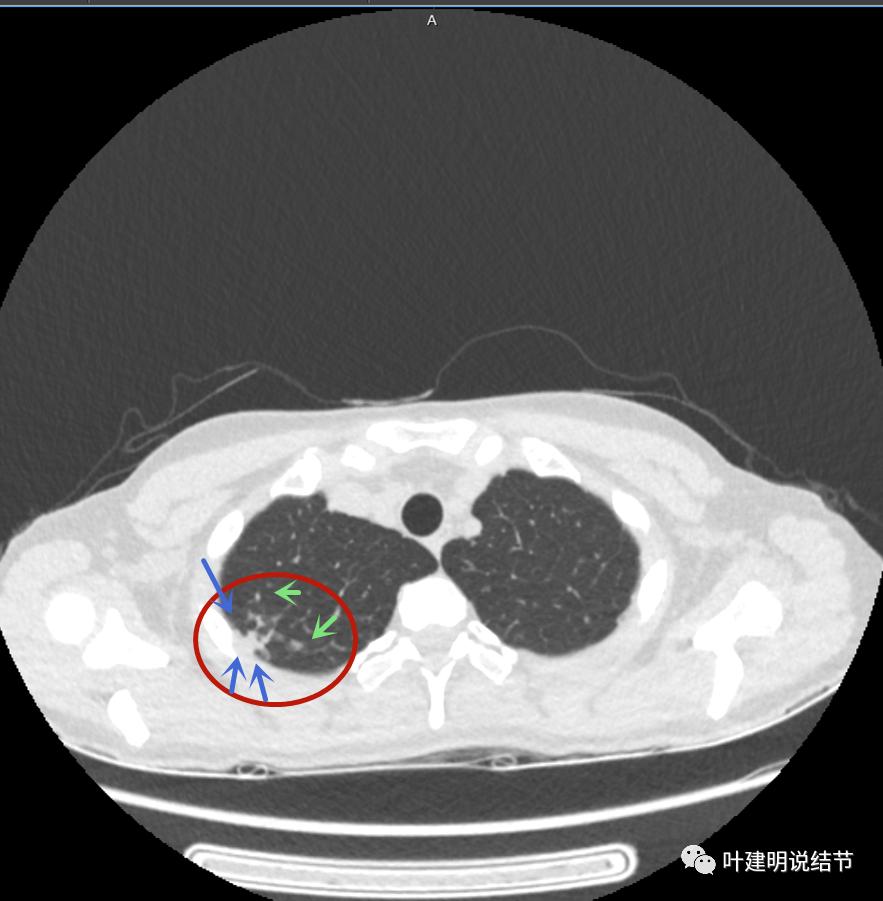

上面是她提供的病史资料,其中最重要的是PPD强阳性!其他主要看影像,我们先来看她2020年7月份的平扫片子(由于片子较多,详细展示是为了同道分析,我在影像特征描述上将只选取部分加以说明):

右肺尖偏实性结节(粉色箭头),邻近胸胸膜明显增厚不平,且广基附在胸壁上(蓝色箭头)

有卫星病灶(绿色箭头)

胸壁侧病灶较厚,模糊(蓝色箭头),仍见卫星灶(绿色箭头)